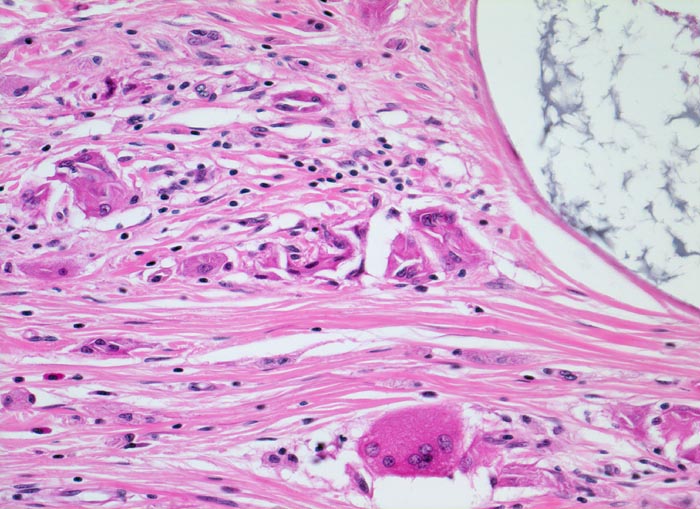

Morphologische Merkmale (2. Präparatlink):

• Tumor bestehend aus einer Mischung reifer epithelialer, mesenchymaler und neuraler Gewebskomponenten:

• Am Rand der Gewebsstücke sind Restanteile von zelldichtem Ovarialstroma mit dickwandigen Gefässen erkennbar.

• Im Gewebefragment rechts lassen sich Drüsen, Knorpelgewebe und Fettgewebe nachweisen.

•  In beiden Gewebsfragmenten finden sich teilweise konzentrisch angeordnete meningotheliale Zellen mit reichlich blass eosinophilem Zytoplasma. Damit assoziiert reichlich psammomatoese Verkalkungen.

• Im linken Gewebsfragment finden sich in der Mitte reichlich Schilddrüsenfollikel sowie eine teils epidermal, teils von Zylinderzellen ausgekleidete Zyste mit Hautadnexstrukturen (Haarfollikel, Talgdrüsen) und einem fokalen chronischen Entzündungsinfiltrat.